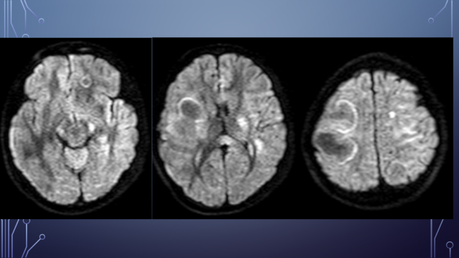

PA: Inicia hace 5 meses con amnesia, cefalea generalizada la cual empeora con el ejercicio, agregándose parálisis facial izquierda por lo que acude con neurólogo privado solicitando TC y posteriormente RM.

El paciente es diagnosticado con EM.

Inicia tratamiento con altas dosis de corticoides.

Deterioro neurológico: parálisis de miembro superior izquierdo y hemiparesia izquierda.